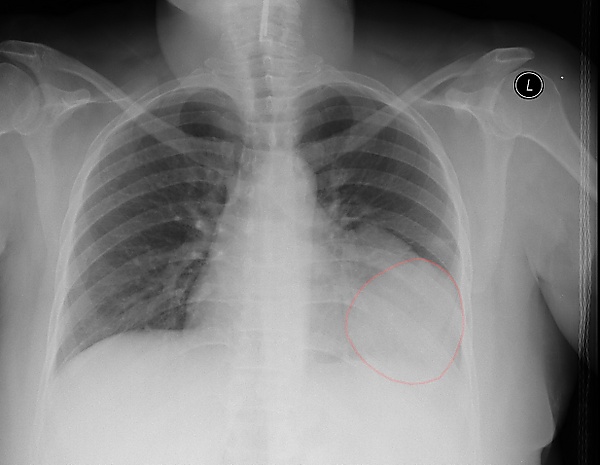

Симптомы зависят от локализации и размеров образования. Большинство проявлений неспецифичны: кашель, боль в груди, нарушение глотания. Гигантские опухоли проявляются медиастинальным компрессионным синдромом: одышка, акроцианоз, отёчность шеи и лица, головная боль, расширение вен грудной стенки и шеи, тахикардия или аритмия, приступы стенокардии[1]. Опухоли средостения могут долго не проявляться и обнаруживаться случайно в ходе диспансеризации или обследования по другим причинам[3].

- рентгенографию органов грудной клетки;

- компьютерную или магнитно-резонансную томографию с контрастированием;